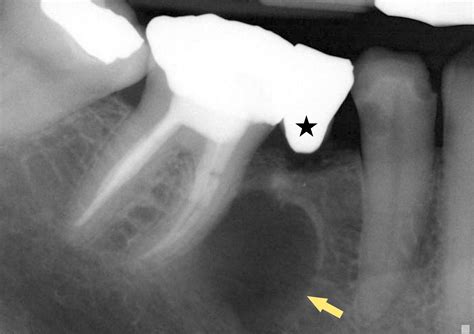

En tamaño, los quistes radiculares suelen medir desde unos pocos milímetros hasta 1 cm de diámetro en promedio, aunque pueden crecer más si persisten por años sin tratamiento. Radiográficamente se observan como una imagen radiolúcida bien delimitada, generalmente redonda u oval, alrededor de la raíz afectada.

A menudo poseen un contorno radiopaco fino y definido (corticalizado) indicando una reacción ósea de delimitación. En casos avanzados, el quiste puede expandir las corticales óseas circundantes, provocar reabsorción radicular de los dientes adyacentes o desplazamiento de estructuras anatómicas (por ejemplo, el piso del seno maxilar en lesiones en molares superiores, o el canal del nervio dentario en mandíbula).

Al palpar, si el quiste es grande, podría notarse una expansión ósea dura e indolora en la zona; si está activo o infectado, podría palparse dolor o fluctuación (indicativa de contenido líquido). La radiografía periapical es la herramienta diagnóstica de primera línea: típicamente muestra una imagen radiolúcida redondeada u oval en el ápice radicular, con bordes bien delimitados y a menudo una fina cortical esclerosada periférica.

Sin embargo, radiográficamente no es posible distinguir con total certeza un quiste radicular de otras lesiones periapicales crónicas (como el granuloma); el tamaño mayor de 1 cm y la presencia de bordes muy definidos sugieren un quiste, pero el diagnóstico diferencial radiológico no es concluyente sin examen histológico.